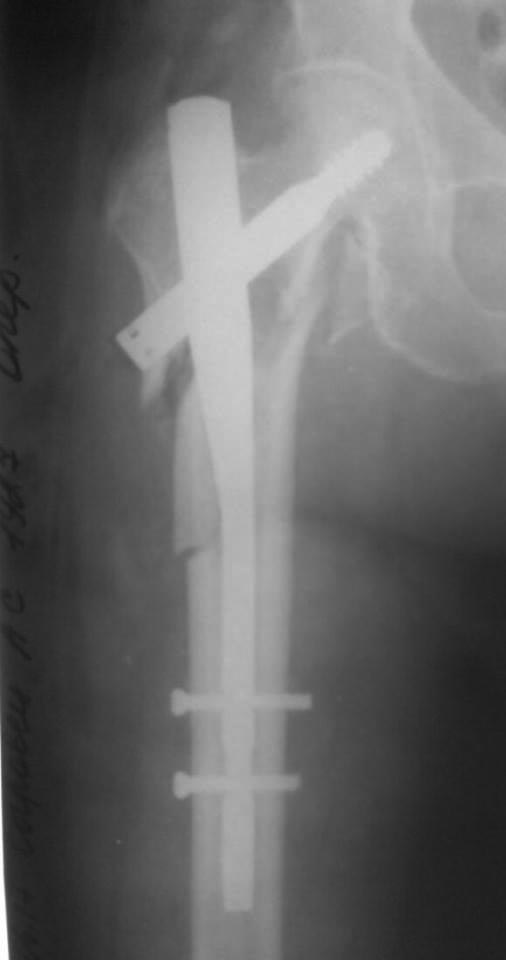

[Ortho] Осторожно! НПП "Имплант", г . Казань

Как-то так